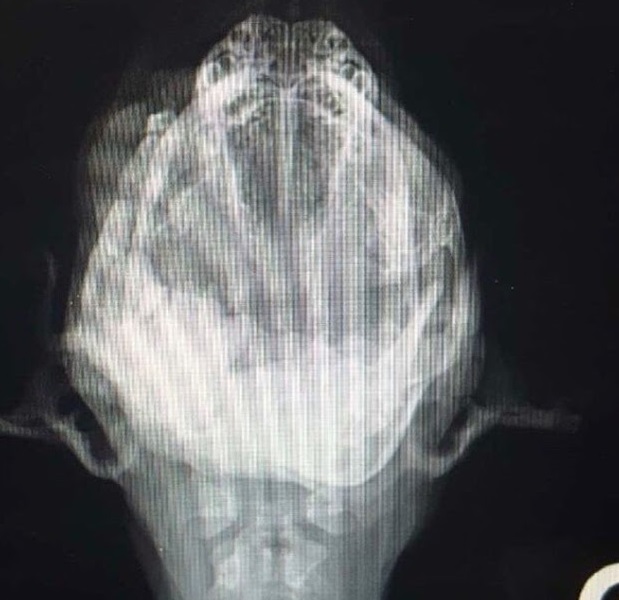

Gdy malec pojawił się przy progach organizacji PMM Rescue Inc., wolontariusze natychmiast dostrzegli rozległe uszkodzenia szczęki. Przeprowadzone badania wykazały, że prawa dolna część szczęki była tak zniszczona i zakażona, iż nie nadawała się do rekonstrukcji.

Infekcja doprowadziła tkanki do nekrozy — martwe fragmenty kości wydzielały odór podobny do gnicia. W tak krytycznej sytuacji jedynym ratunkiem była resekcja zainfekowanych tkanek. Lekarze weterynarii, by uratować życie Arrowa, musieli usunąć całą prawą część dolnej szczęki oraz fragment prawej strony szczęki górnej.

Kto uratował Arrowa? Chirurg weterynarii Dr Sidhu z Bakersfield w Kalifornii podjął się złożonego, czasochłonnego zabiegu. Nie odszedł od boków pacjenta, dopóki nie upewnił się, że maluch ma realną szansę na powrót do zdrowia.